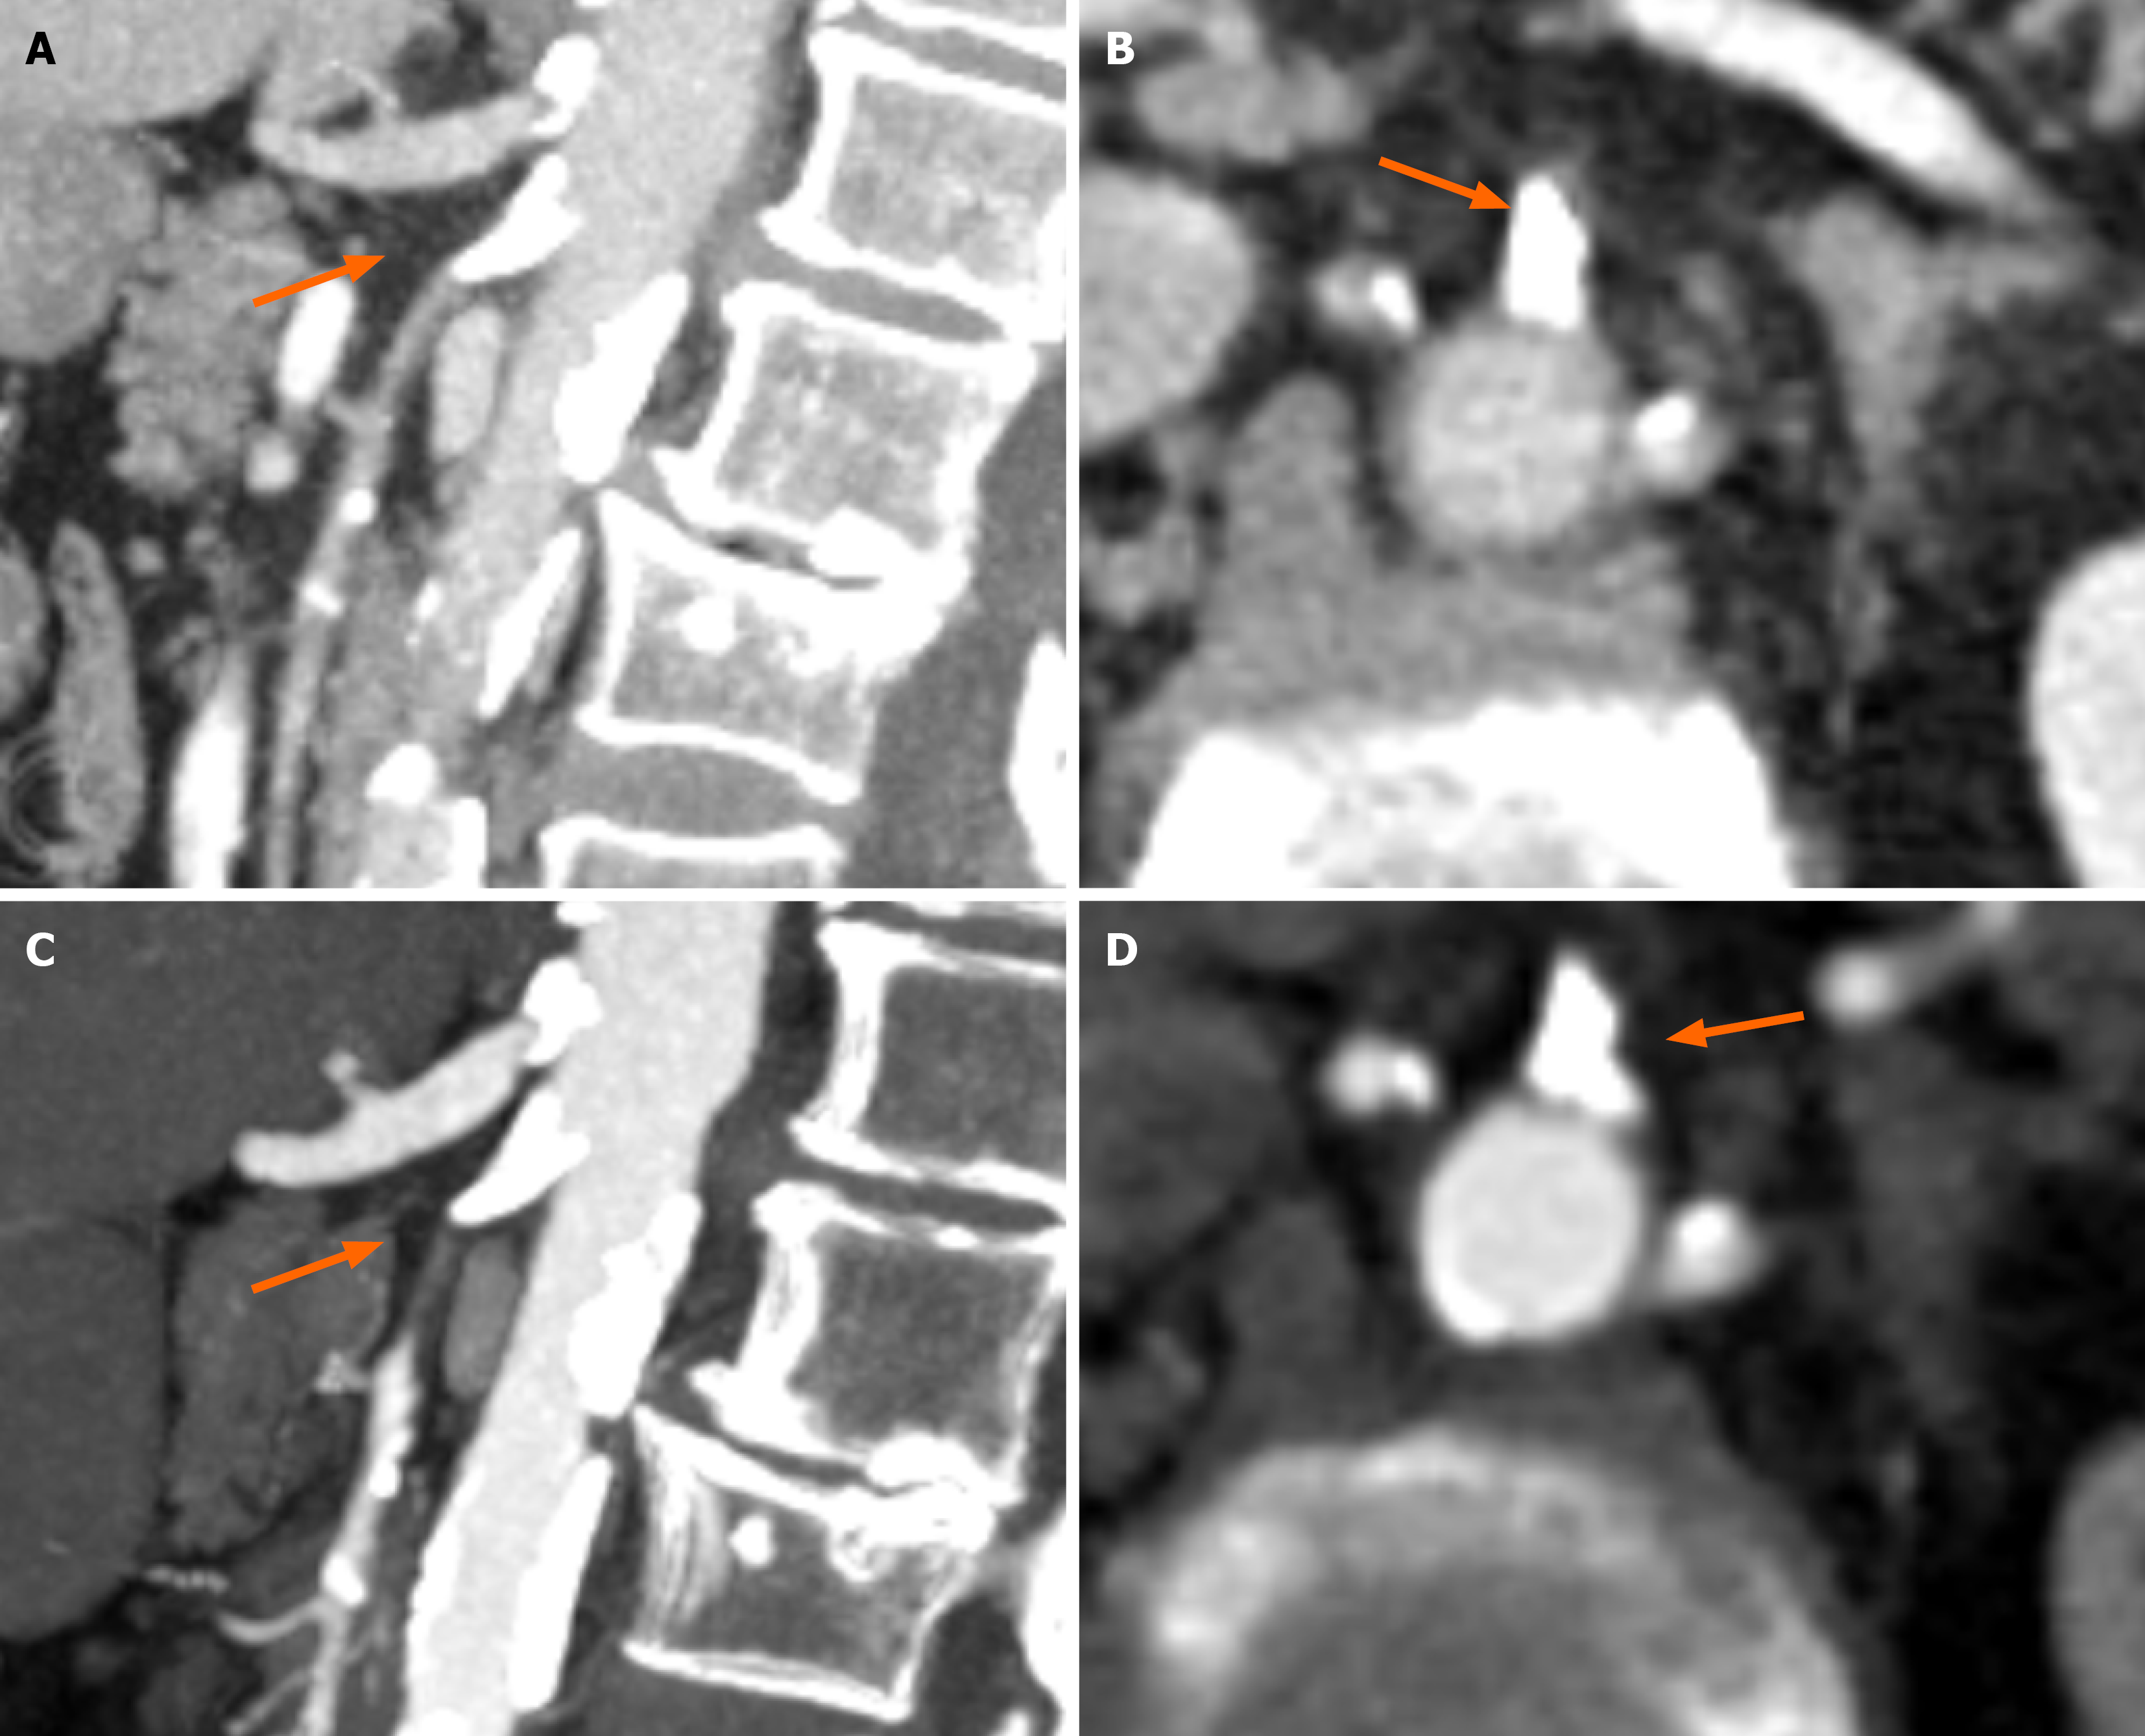

Case 2: The abdominal CT performed for investigation of the patient´s symptoms several months prior was re-reviewed by the gastroenterology registrar, revealing marked calcification at the SMA and celiac origins, not mentioned in the radiology report (Figure 2A and B). CT angiography confirmed high-grade stenosis of the SMA (Figure 2C and D). Figure 2A and B (CT abdomen protocol) show the presence of significant calcification at both the celiac trunk and SMA (Figure 2A, sagittal reconstruction), with extensive calcification at the SMA ostium when viewed in axial view. The SMA show extensive calcification along the entirety of its length especially in sagittal view. Figure 2C and D (CT angiography protocol) show extensive calcifications at both the celiac trunk and SMA (Figure 2C, sagittal reconstruction). Panel D shows extensive calcification at the SMA ostium when viewed in axial view.